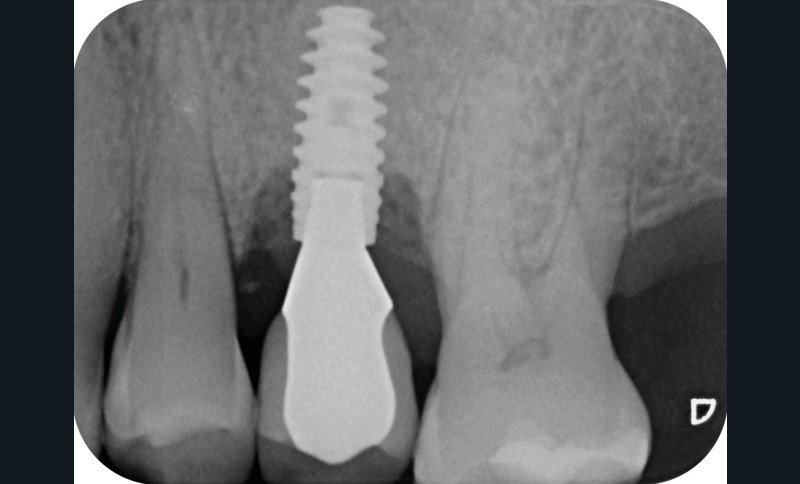

- Posé en 2019 par son dentiste

- Couronne d’usage transvissée

- Péri-implantite diagnostiquée en 2020